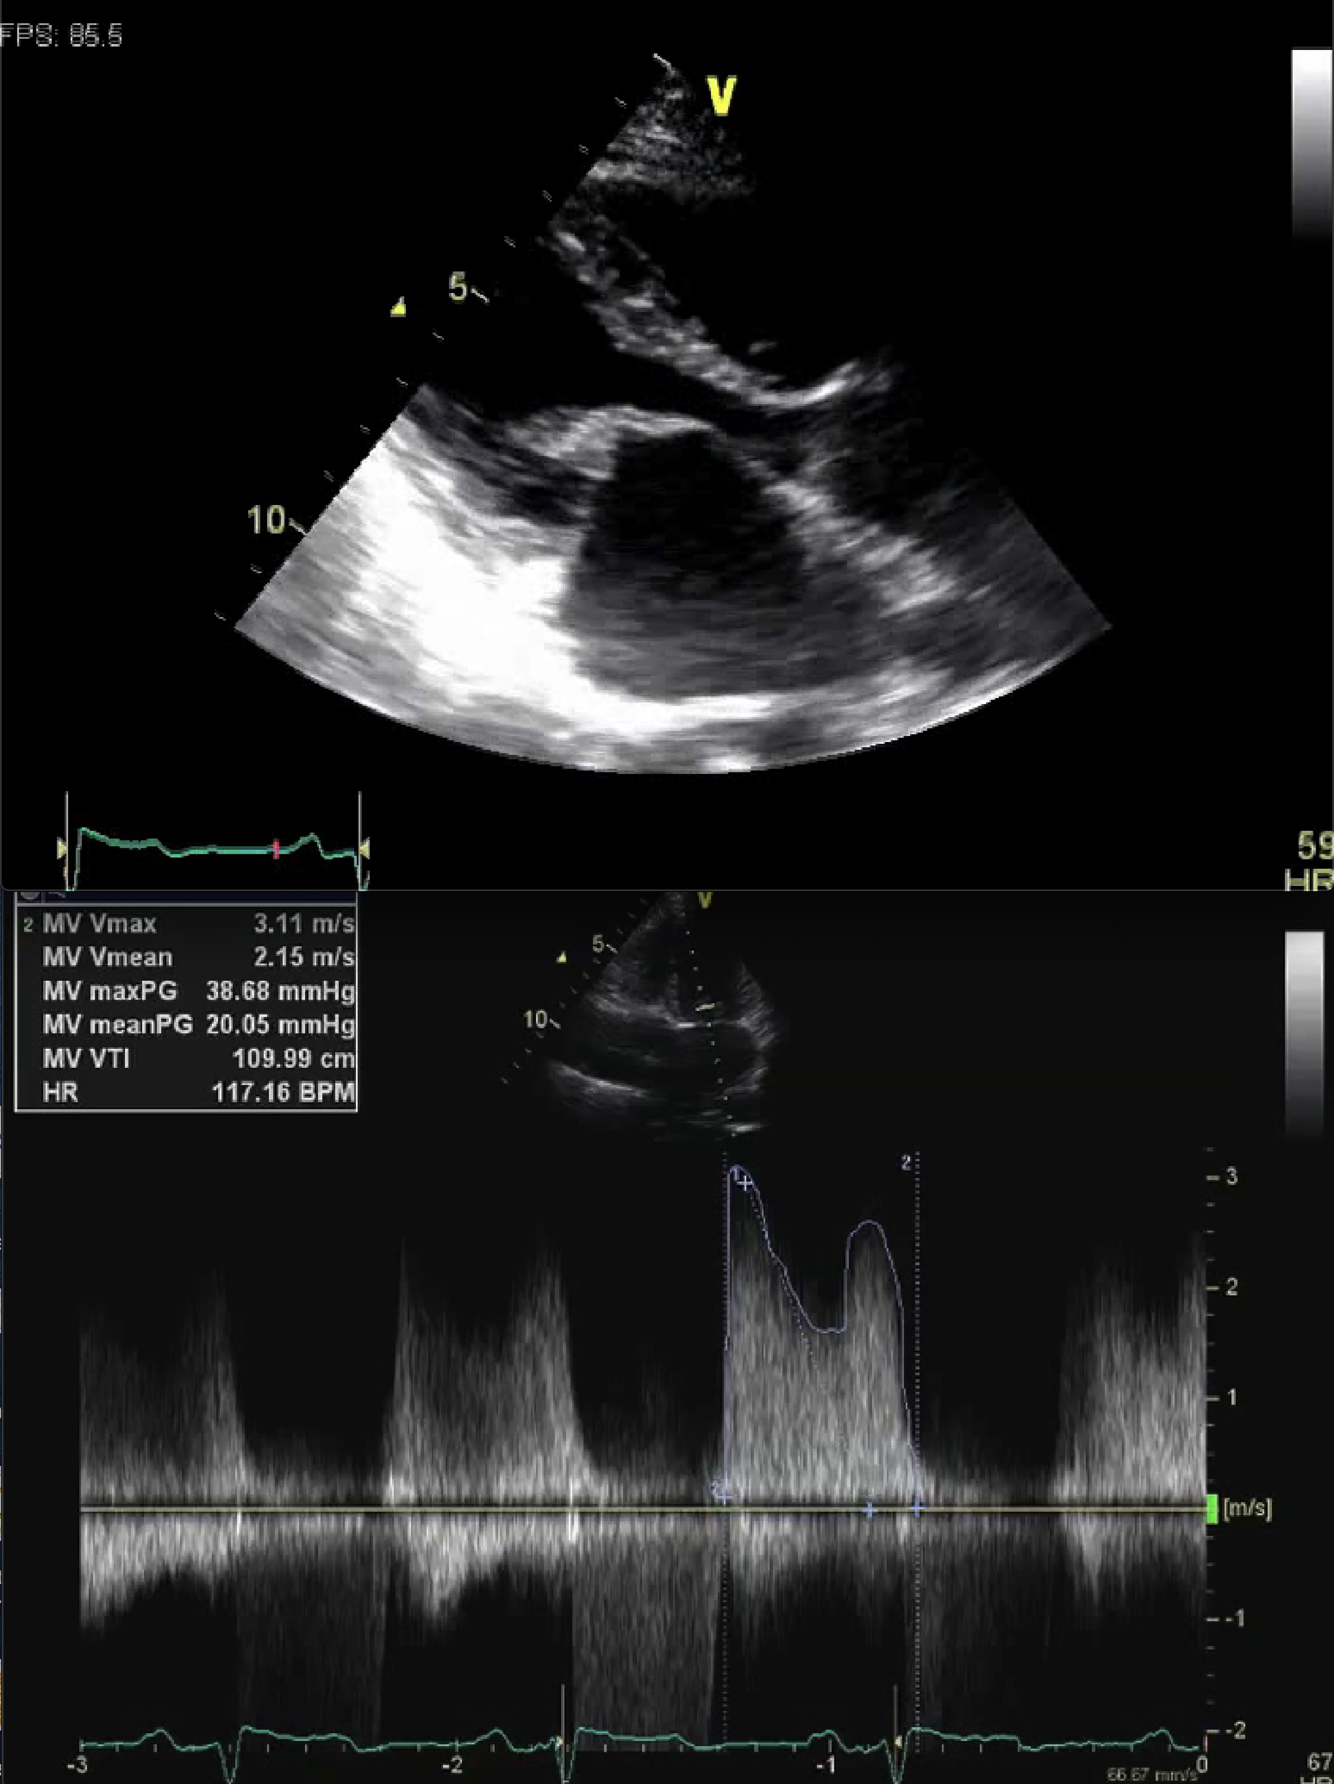

Describe the findings: